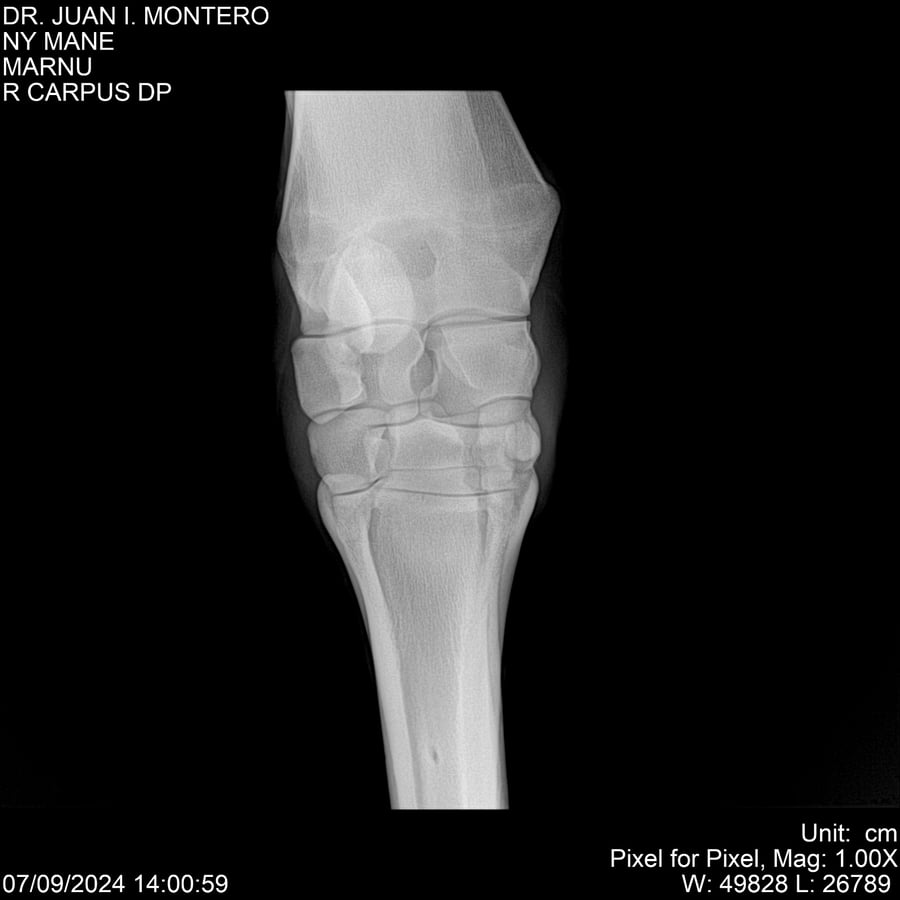

LOTE 20, NY MANE Lote Anterior Volver al remate Lote Siguiente Ficha Contacto Montevideo - Ficha del Lote Identificador: #282520 Categoría: Yeguarizos 76 Visualizaciones ClicData Contacto Empresa: Abelenda N. R., Walter Hugo Nombre*: Teléfono* : E-mail* : Mensaje Enviar Registrese gratis Este contenido Exclusivo está disponible sólo para usuarios registrados Ingresar